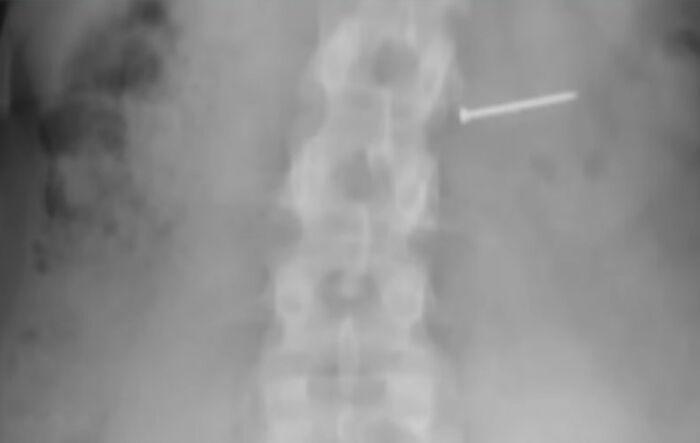

Yapılan röntgen ve detaylı incelemeler sonucunda Buckley’in yuttuğu şeyin basit bir yiyecek parçası değil, metal çiviler ve keskin parçalar olduğu ortaya çıktı. Sindirim sistemine zarar veren bu yabancı cisimler, kadının iç organlarında ciddi hasara yol açtı.